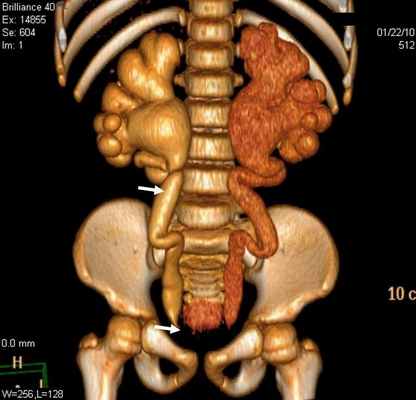

Специальная программа позволяет реконструировать полученные данные в любой иной плоскости или воспроизвести трехмерное изображение органа или группы органов. Проведение МСКТ позволяет получить трехмерное изображение сосудов почки, чашечно-лоханочной системы, мочеточника и мочевого пузыря. Разработка и внедрение метода МСКТ значительно повысили диагностические возможности в выявлении пороков развития уретеровезикального сегмента.

Результаты исследования и их обсуждение. Показаниями к выполнению МСКТ были расширение мочеточника. В 29 (78,4%) наблюдениях выявлен уретерогидронефроз различной степени, в 5 (13,5%) – эктопия устья мочеточников и в 3 (8,1%) - уретероцеле (рис. 1).

Уретероцеле обнаружено у 3 (8,1%) пациентов из 37. Этот порок уретеровезикального сегмента на МСКТ характеризовался с кистовидным расширением внутрипузырного сегмента мочеточника. При этом отчетливо определяется округлая полость, вдающаяся в просвет мочевого пузыря (рис. 3).

Рис 3. МСКТ картина уретероцеле. Трехмерная реконструкция. Удвоение почек и мочеточника справа (a) и уретероцеле слева (б)

Во всех наблюдениях устья мочеточников открывались в мочевой пузырь. В отличие от экскреторной урографии на МСКТ четко определяются изменения со стороны почек и мочеточника, особенно при трехмерной реконструкции.

Стеноз устья мочеточника на МСКТ выявлен в 29 (78,4%) наблюдениях (рис 4). Данная патология у 17 детей была с обеих сторон, а 3 наблюдениях этот порок сочетался с уретероцеле и эктопией устьев мочеточника.

Рис 4. Стеноз устья мочеточника. Трехмерная реконструкция. Больной К., 6 лет. Деформирование мочеточников и сужение устья мочеточников